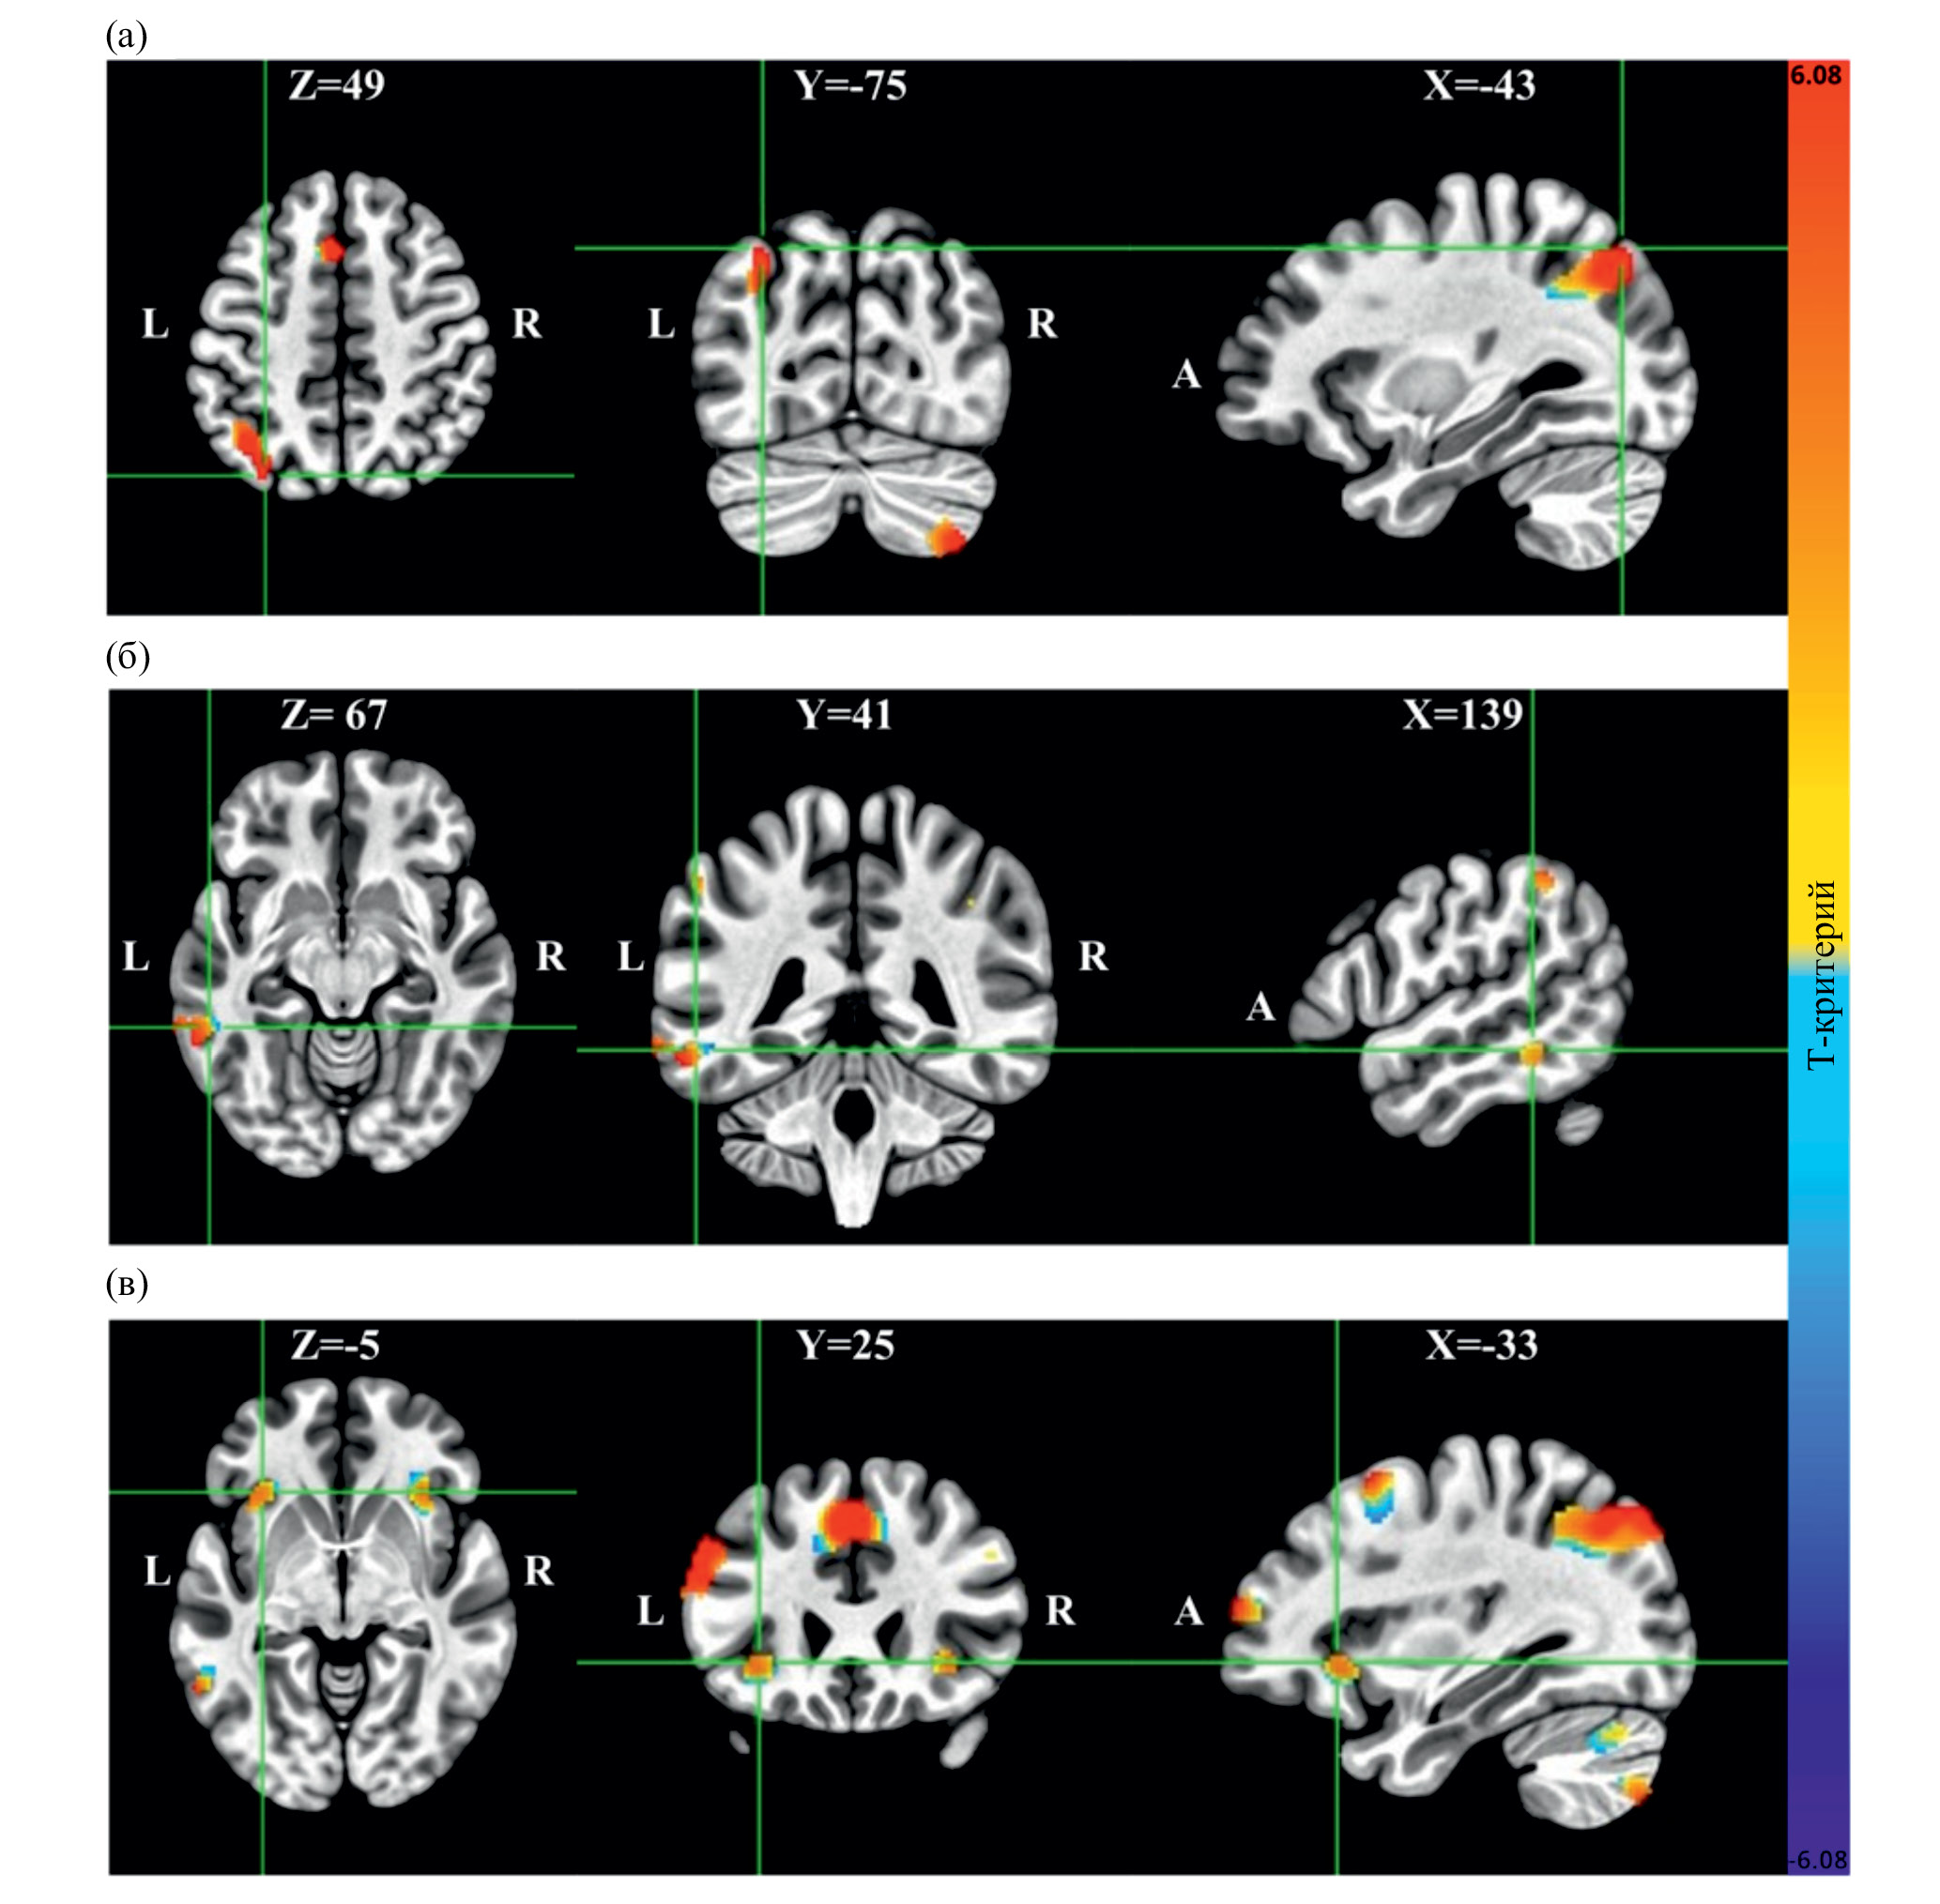

Functional magnetic resonance imaging (fMRI) was conducted during the mental calculation of tasks involving basic arithmetic operations at three difficulty levels. During the solving of arithmetic problems involving subtraction, multiplication, and division at the easy level, brain activity was observed in the left inferior parietal lobule and left angular gyrus, which may reflect the memory retrieval from long-term memory. Additionally, activity was detected in the left inferior frontal gyrus during division, indicating using the procedural strategy. As the task difficulty increased, brain activity in the left inferior parietal lobule and left angular gyrus became bilateral and more intense, with additional involvement of structures such as the superior frontal gyrus, supplementary motor area, inferior middle and temporal gyri, as well as the cerebellum, indicating the need for increased neural resources to solve more difficult tasks. Bilateral activity was identified in the insular cortex during the solving of three-digit division tasks, which is associated with various affective and cognitive processes. Many areas underlie mathematical performance in adults which highlight the different systems involved in solving arithmetic problems of varying complexity. Despite similarities in brain activation patterns, behavioral results showed statistically significant differences between arithmetic operations. The results of the study add to existing knowledge on neuromaping of math cognition.